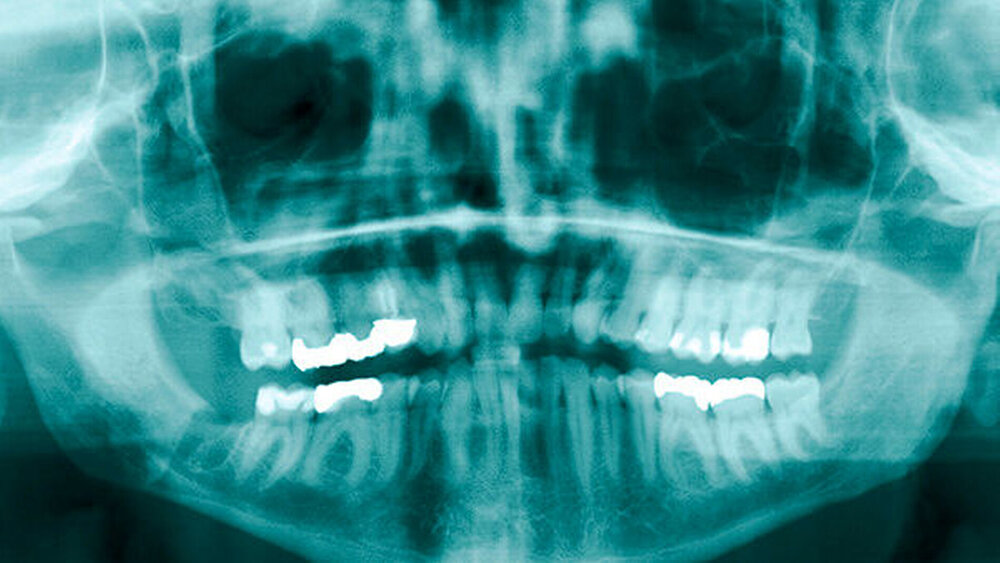

Zur bildgebenden Diagnostik erfolgten ein Orthopantomogramm und alio loco eine Zahnfilmaufnahme, bei der sich der dislozierte Wurzelrest des Zahnes 48 circa 3 mm kaudal der Alveole projizierte. In der durchgeführten digitalen Volumentomografie stellte sich der Wurzelrest kaudal der Linea mylohyoidea und medial der Tuberositas pterygoidea im Bereich der rechten Submandibularloge dar (Abbildungen 1 bis 4). Die operative Entfernung des Wurzelrests erfolgte durch einen transoralen Zugang in nasotrachealer Intubationsnarkose. Als operativen Zugang in den posterolateralen Mundboden beziehungsweise in die Submandibularloge rechts wurde der bestehende gingival geführte Winkelschnitt durch einen lingualen Zahnfleischrandschnitt aus regio 47 bis 43 sowie durch eine transversale Verbindung disto approximal 47 erweitert. Die daraus resultierende H-förmige Schnittführung erlaubte die subperiostale Darstellung des Ramusvorderrands und das retrograde (von der Koronoidkerbe ausgehende) Auslösen des lingualen Weichgewebes zur Bildung eines lingualen Mukoperiostlappens. Nach stumpfer Präparation einer Kavität entlang der lingualen Innenkortikalis und um die konvexe Kontur des retromolaren Knochenbalkons bis auf die Kranialfläche des M. mylohyoideus wurde der Muskel im Dorsalbereich seiner Insertionslinie mit der Schere scharf abgetrennt, um die Submandibularloge von kranial zu eröffnen. Die Retraktion des Mukoperiostlappens nach intermaxillär führte zur übersichtlichen Exposition der gesamten Retromolarregion und der Möglichkeit, unter Schonung des N. lingualis in die Submandibularloge einzugehen (Schnittführung siehe Abbildung 5). Im lingualen Kortex der Alveole regio 48 wurde eine Perforation in den Mundboden von etwa 6 bis 7 mm Durchmesser als Durchtrittsstelle für den Wurzelrest identifiziert (Abbildung 6).